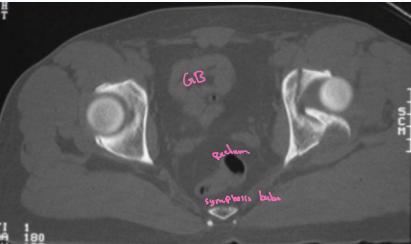

Imaging:

- X-ray & CT scan

- R/O an acetabular fracture (or intraarticular bony fragment)